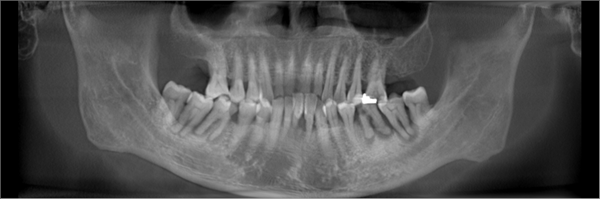

但随着年纪增大, 我牙齿逐渐松动脱落, 更糟糕的是我喜欢咬硬东西, 牙齿磨损得厉害,有一次不小心就把牙齿给咬断了。不仅痛,还刺激到牙神经很不舒服。拔了几颗牙齿之后,吃东西咀嚼都很艰难,味道也跟之前完全不同了。档期满满的,缺牙问 题 一 直 没有时间解决,让我非常困扰。牙齿缺失随之而来的是说话漏风、台词都念不准,我担心无法呈现最完美的一面给观众。

刚考虑种牙的时候,我也跟大家一样各种担忧,担心种牙痛不痛、 安不安全,等等……作为公众人物,我经常有机会访问国内的医疗机构, 在综合对比后我发现,麦芽的各项设施和技术都处于行业领先水平,设备齐全,环境干净,最重要的是他们还拥有一支由硕博专家领衔的医疗团队。